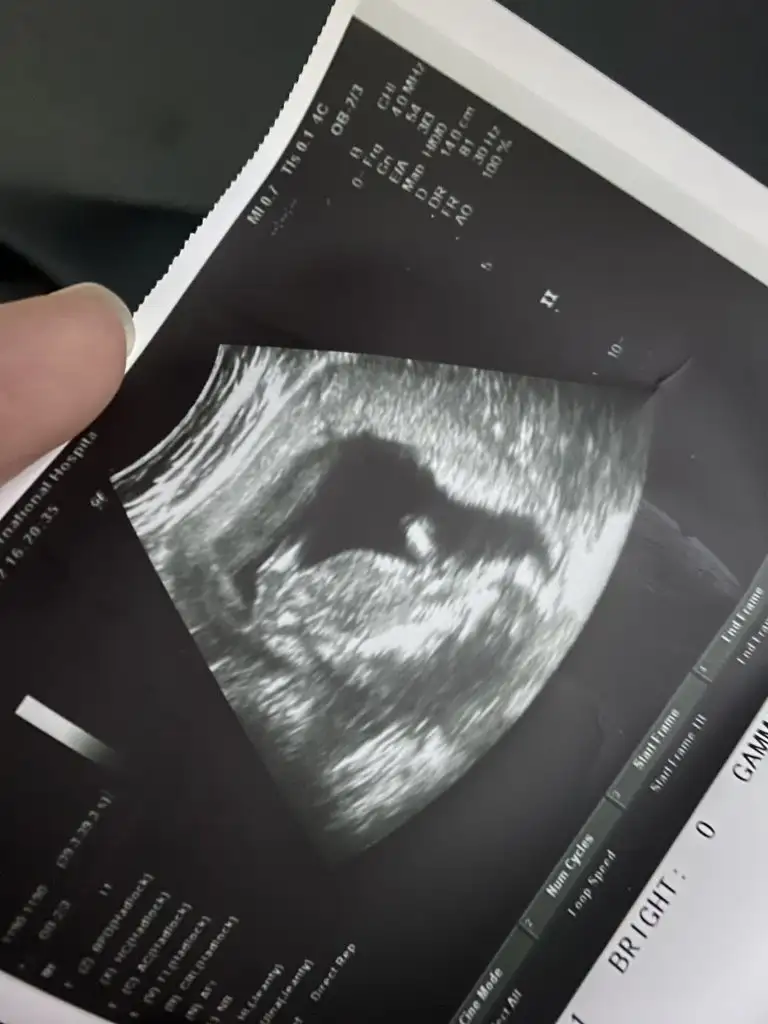

canım bılıyorsunkı benım betalar senınkındende yuksek gıttı hatta ıkızmı dedıkKızlar benim 14+6 100 grammış zayıf demekki size göre , cinsiyet de belli oldu ama sürpriz öğrenicem hafta sonu zarfta yazılı bekliyorum öyle. Bulantıya göre cinsiyet olur mu bilmiyorum ama dört ay bitecek neredeyse hala çok kötü bulantılarım yiyemiyorum zayıf kaldı çocuk . Benim beta çok yüksek başlamıştı o zaman erkek mi diyosunuz teorilerinize göre fotoğrafta hiç bişey belli olmuyor . Bir de hissedenlere ne mutlu keşke ben de hissetsem yakında ya .